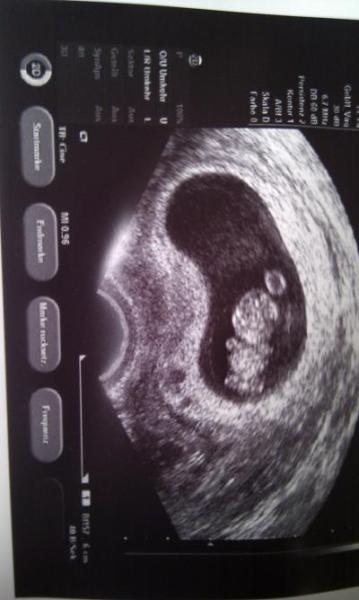

Hallo ihr lieben Nach 4 langen Wochen hatte ich nun heute mein 2.Termin beim FA. Hatte solche Angst das irgendetwas nicht stimmt!!! Aber alles ist supi.... Bin heute in der Regel bei 9+2. Mein Arzt war soo überrascht das sich der Bauchzwerg so doll bewegt hat.:) Hat sich richtig viel bewegt und gewunken. Bin total glücklich!!! Beim messen war der Zwerg auch schon viel größer. Habe aber keine Maß. Schließlich sagte der FA das ich eine Woche weiter bin... also 10+2... Damit hätte ich nie gerechnet.. Meinen Mutterpass bekomme ich nun in 2 Wochen. Ein Bildchen habe ich auch bekommen. Sieht total süß aus.....* träum*

Bild zu bin zurück .... - Forum für September - Mamis

Noch so ein süßes Gummibärchen. Ich freue mich für Dich und bin schon tierisch auf meinen Termin, morgen früh gespannt. LG Dani